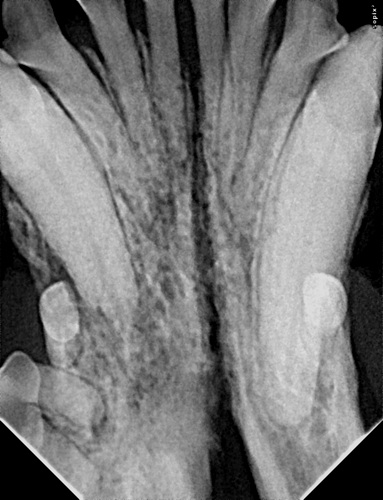

Too Many Teeth in Dogs and cats

Too Many Teeth in Dogs and cats from my.vetmatrixbase.com

Kittens lose baby teeth between three and four months. New, permanent teeth are whiter, thicker and larger than baby teeth. Learn how to help ease kitten teething. Retained deciduous teeth occur when the roots of certain deciduous teeth, usually the canines, incisors, or premolars, do not resorb fully or at all.